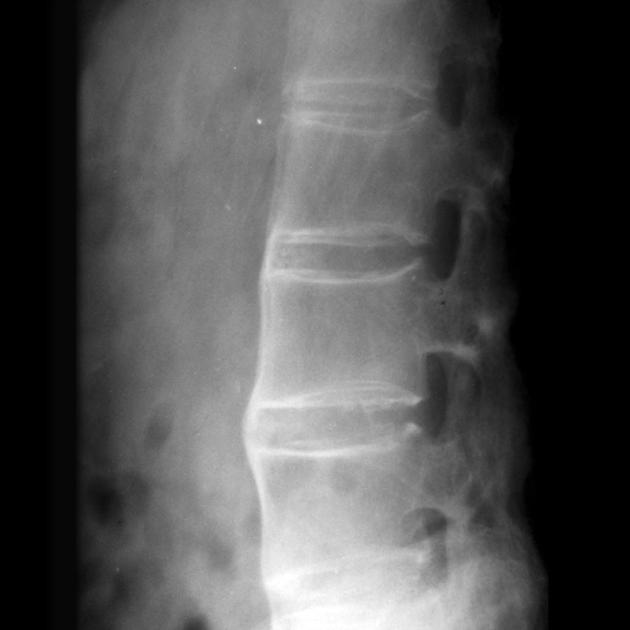

二、脊柱活动度受限评估

随着疾病的进展,脊柱的活动度会逐渐受到限制

这种限制不是一夜之间发生的,而是一个渐进的过程,就像温水煮青蛙一样,让人不易察觉